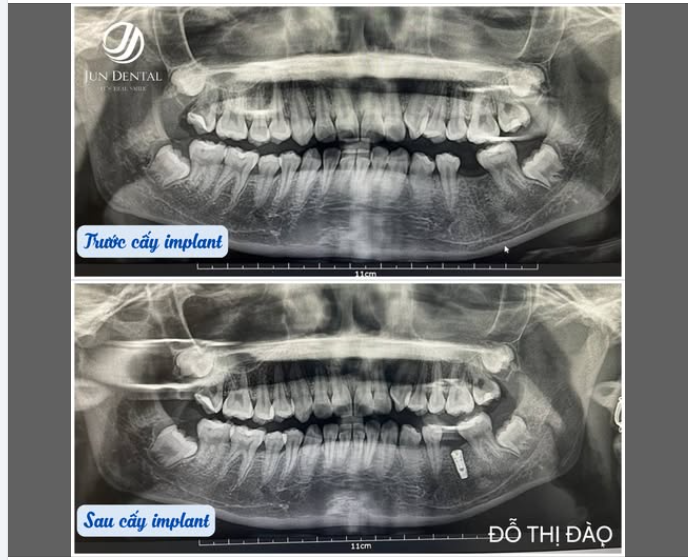

CA CẤY IMPLANT – KHÁCH HÀNG ĐỖ THỊ ĐÀO